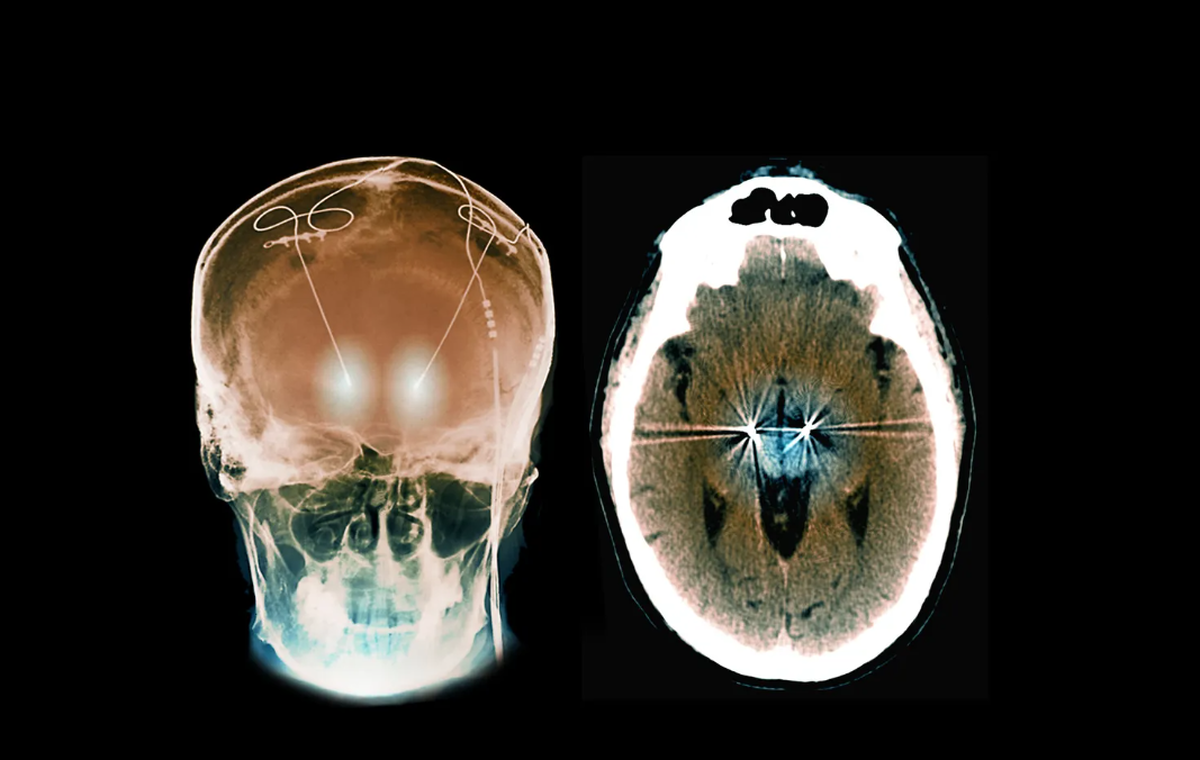

همزمان، تصویربرداری عصبی نیز نشان داد که سیناپسها در نواحی آسیبدیده مغز بهطور قابل توجهی بازسازی شدهاند. سیگنالهای الکتریکی در نورونها نیز به سطح طبیعی بازگشت.